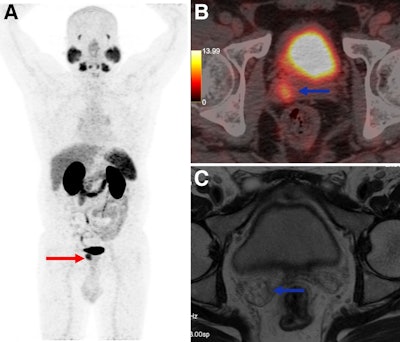

A 55-year-old man presenting for initial staging of prostate cancer. (A) Ga-68 PSMA-11 PET/CT maximum-intensity projection shows PSMA-expressing lesion involving prostate (red arrow), with PSMA avidity in right seminal vesicle invasion (blue arrow). (B) PET/CT axial image shows right seminal vesicle invasion (blue arrow). (C) However, MRI at same topography shows no seminal vesicle invasion. Pathology analysis confirmed Ga-68 PSMA-11 PET/CT-positive results.A 55-year-old man presenting for initial staging of prostate cancer. (A) Ga-68 PSMA-11 PET/CT maximum-intensity projection shows PSMA-expressing lesion involving prostate (red arrow), with PSMA avidity in right seminal vesicle invasion (blue arrow). (B) PET/CT axial image shows right seminal vesicle invasion (blue arrow). (C) However, MRI at same topography shows no seminal vesicle invasion. Pathology analysis confirmed Ga-68 PSMA-11 PET/CT-positive results.Journal of Nuclear MedicineAccording to the results, Ga-68 PSMA-11 PET/CT detected metastatic disease (M1) in 20.4% of cases, altering management and preventing prostatectomy in 24% of patients. The accuracy for seminal vesicle invasion was 90.1% for Ga-68 PSMA-11 PET/CT versus 57.3% for MRI, and for lymph node metastases it was 91.1% for Ga-68 PSMA-11 PET/CT versus 69.7% for MRI.